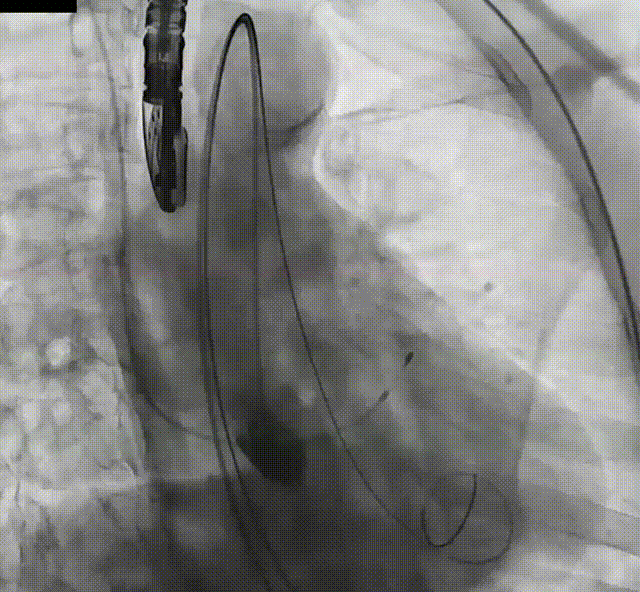

瓣膜缓慢脱钩

术后造影评估

停起搏,缓慢释放瓣膜脱钩。观察几分钟,TaurusElite®AV29mm瓣膜锚定良好,未下滑。术后造影结果显示瓣膜形态、位置良好,无瓣周漏。手术即刻超声测量,主动脉瓣工作良好,无反流。